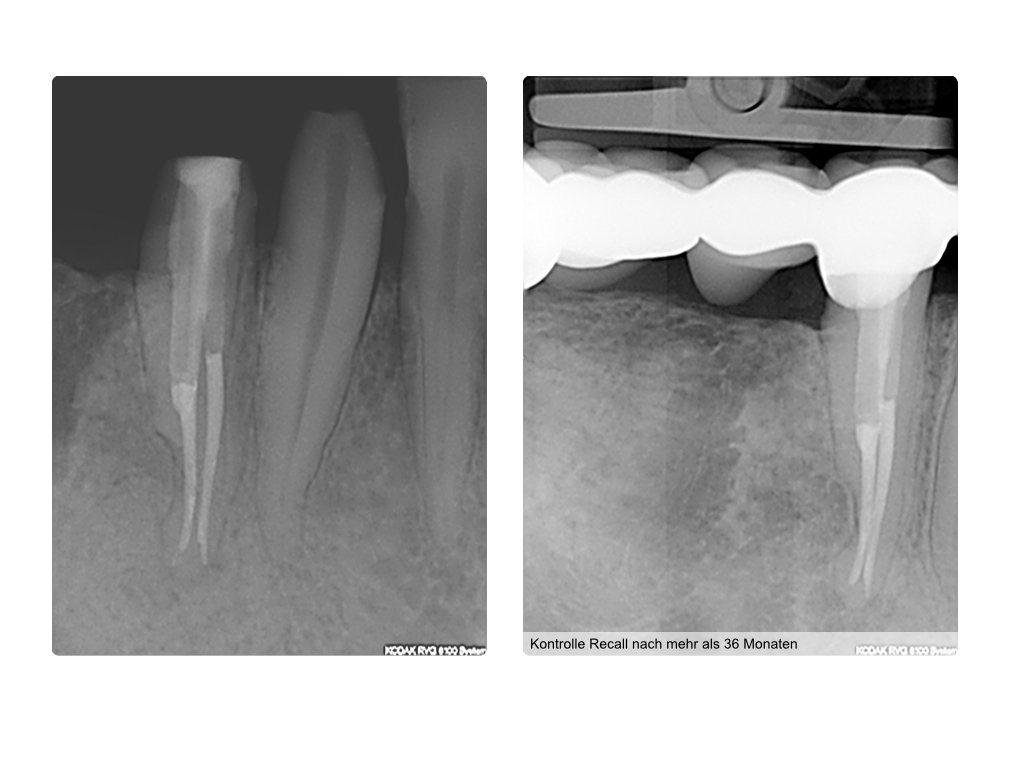

WS_Fallvorstellung 10.003

Merkwürdiges Röntgenbild